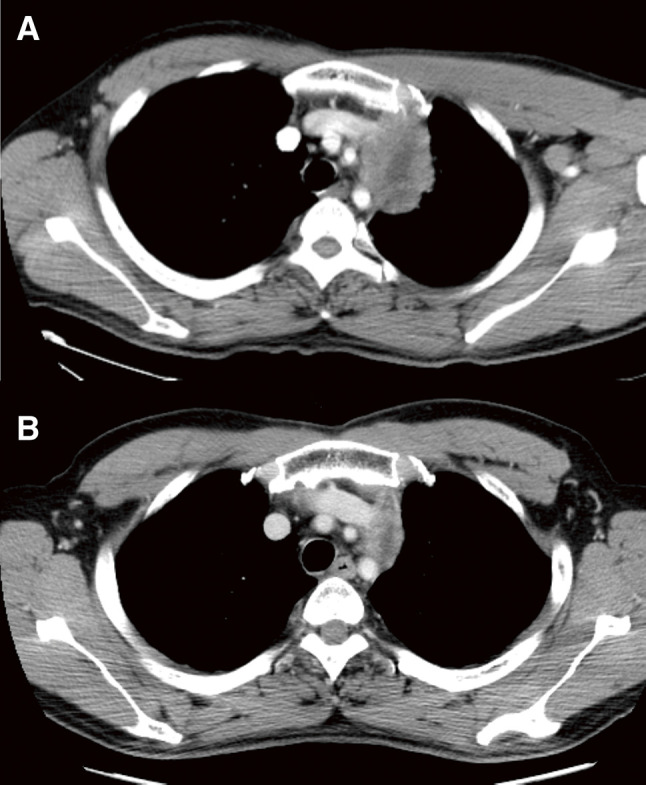

Case presentation: A 46-year-old man with no history of malignancy was diagnosed with anterior mediastinal adenocarcinoma through biopsy. The patient underwent chemoradiation for the tumor, which was initially suspected as invasive T4 lung cancer. After a favorable response to presurgical therapy, the tumor was deemed more likely a mediastinal tumor, and it was completely resected simultaneously with the thymus, the partial left lung, and the partial left innominate vein. The tumor contained histologic features identifiable as a lymph node tissue and lacked any thymic tissue, which led to the final diagnosis as metastatic lymph node adenocarcinoma; however, its origin was unknown. No signs of recurrence were detected for 13 years after surgery.